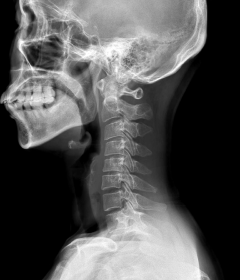

정상적인 목뼈는 C자 형태의 굴곡을 지니고 있습니다. 이를 "전만"이라고 합니다.

그러나 잘못된 자세나 생활습관으로 인해 목뼈의 모양이 일자로 곧게 뻗은 경우는 '일자목 증후군'이라고 하며, 더 심한 경우는 반대 C자 형태 즉, 역 C자 형태의 목을 '거북목 증후군' 또는 '자라목 증후군'이라고 합니다. 이는 의학적으로 경추 후만증으로 일컫습니다.

정상목

거북목